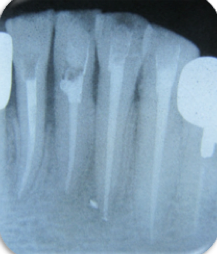

症例(マイクロスコープを用いた歯の根の治療:破折ファイルの除去)